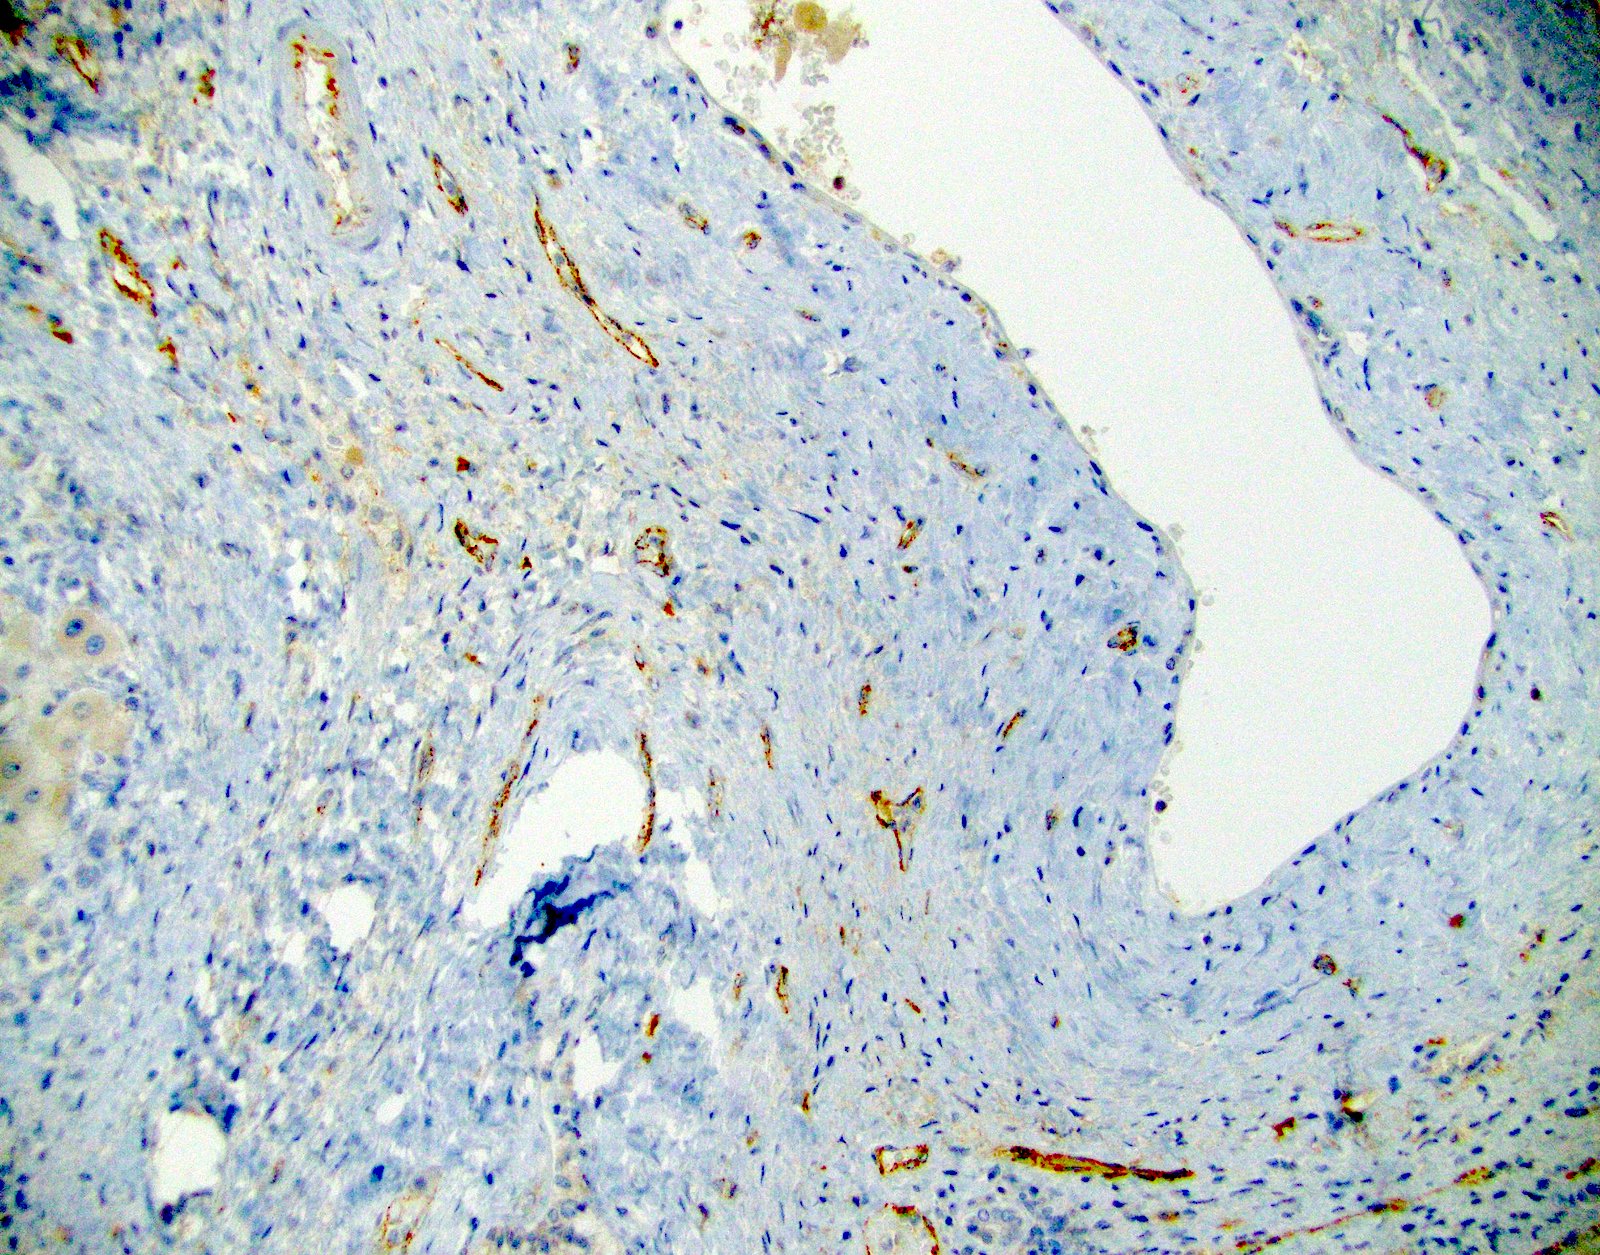

Positive stains

- Focal to diffuse C4d uptake by portal microvasculature (portal veins and capillaries) that may extend to inlet venules

- C4d on paraffin tissue: diffuse uptake by portal microvasculature (portal vein and capillaries) and inlet venules